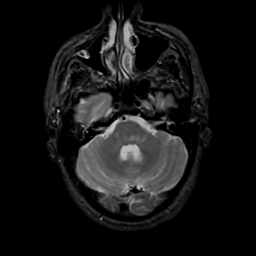

MR Study #15, June 9, 1991 -- Slice #12